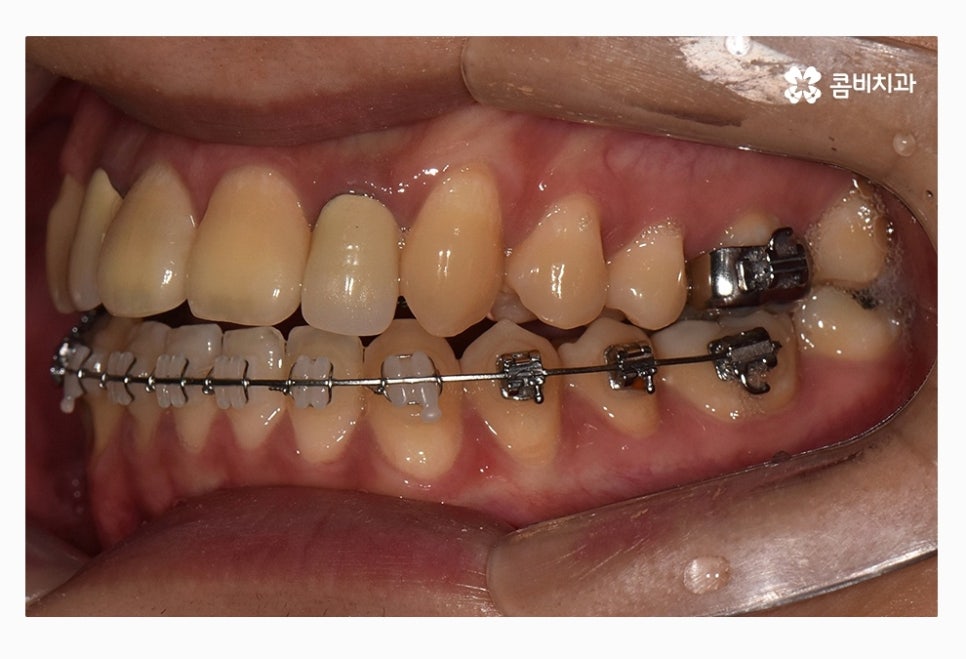

위 사진을 다시 한번 자세히 보면 윗니는 치아의 안쪽에

교정 장치가 부착이 되어 있는 모습이며

아랫니는 일반적인 교정 방법으로 장치가 부착되어 있어요.

위 사진은 교정 장치를 부착한 초기 사진이며

아래는 콤비교정 진행하고 약 1년 정도 지난 후 사진이라고 할 수 있는데요.

윗니에서 앞니가 유독 삐뚤어져 있던 상황이었는데

반듯하게 자리를 잡아가고 있으며 아랫니에서도

삐뚠 부분이 있었는데 가지런하게 자리를 잡아가고 있어요.